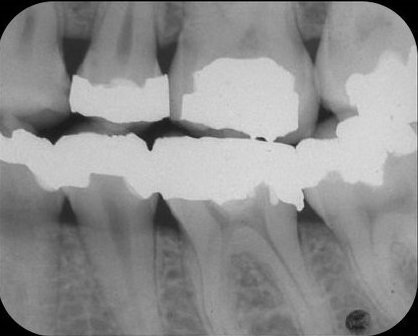

Tijdens het zoeken van de kanaalingangen met een ronde boor veroorzaakte ik een perforatie naar mesiaal (afb. 2), die zichtbaar werd nadat ik een lengtefoto had genomen, waarbij een vijl door de mesiale begrenzing van de mesiale radix stak.

Afb. 2: Lengtefoto van de mesiale kanalen, waarbij een handvijl in de perforatie steekt